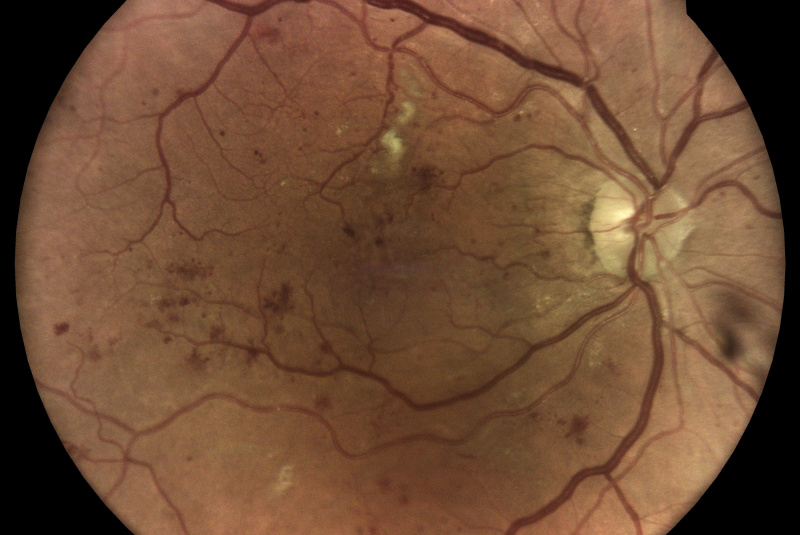

Technologie TrueColor Confocal společnosti iCare překonává limity běžných zařízení pro zobrazování fundu a SLO (scanning laser ophthalmoscop) tím, že kombinuje nejlepší výhody obou. Jednoduše řečeno, fundus kamery poskytují vysokou barevnou věrnost a SLO systémy vytvářejí vysokou ostrost, jasnost, celkovou přesnost a detailnost snímků. Když se tyto vlastnosti zkombinují, vznikne špičkový obraz sítnicové krajiny ve věrných barvách.

Pro diagnostiku a sledování běžných patologií, jako je diabetická retinopatie, musí být zařízení pro zobrazování očního pozadí schopna kombinovat vysoké rozlišení, vysoký kontrast a vysokou barevnou věrnost. To umožňuje zachytit drobné rysy a detaily a rozlišit jednotlivé změny, které byste jinak mohli snadno přehlédnout. Zatímco standardní systémy SLO mají vysokou jasnost, ostrost a kontrast, tradiční fundus kamery nabízejí vysokou barevnou věrnost, běžná zobrazovací řešení tyto dvě věci nekombinují!

Monochromatické lasery používané ve standardních SLO systémech mohou díky konfokálnímu optickému mechanismu poskytovat vysoce ostré a kontrastní snímky. Na druhou stranu však nedokážou zachytit sítnici v jejích skutečných barvách.

Systémy pro zobrazování fundu vytvářejí snímky přirozených barev pouze tehdy, pokud používají bílé světlo: to znamená, že v osvětlovacím paprsku používaném k zobrazení sítnice jsou přítomny všechny vlnové délky viditelného spektra. Na získaném snímku lze rozlišit různé barevné detaily.

Naproti tomu systémy využívající monochromatické zdroje světla, jako jsou systémy SLO, používají k osvětlení sítnice pouze určité vlnové délky. Poskytují proto pseudobarevné obrazy, které postrádají některé spektrální složky, a výsledkem jsou chybějící informace nebo barevné artefakty.

Systém iCare se vyznačuje použitím bílého LED světla v kombinaci s konfokální optikou, což pomáhá získat vysoce kvalitní snímky sítnice se zvýšenou barevnou věrností.